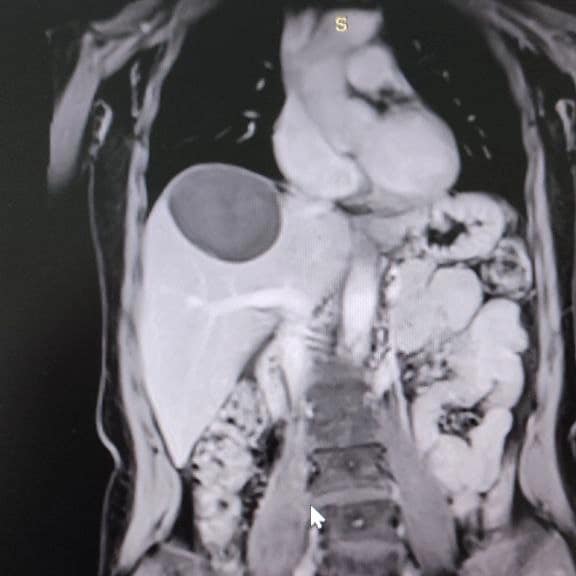

50-річна жінка зі скаргами на тиснення і біль у правому підребер’ї поступила у Володимирське ТМО. У неї діагностували небезпечне захворювання - ехінококову кісту, яку хірургічно видалили.

Паразитарна кіста в печінці нагадує навколоплідний міхур, всередині якого дозрівають личинки ехінокока. Новоутворення поступово зростає і часом досягає гігантських розмірів (до 50 см у діаметрі).